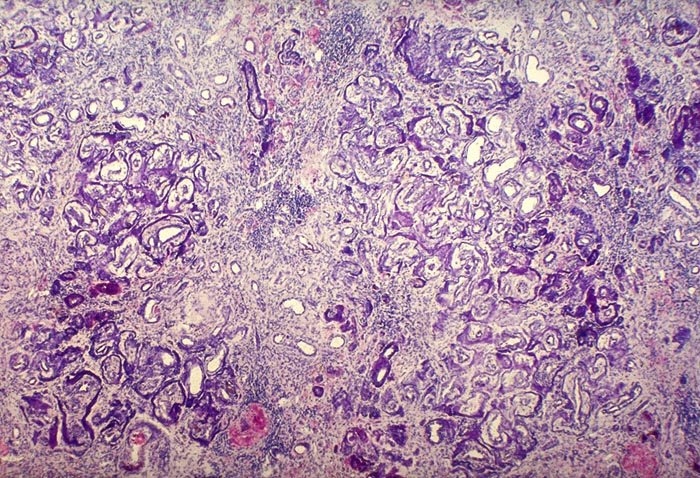

Nephrokalzinose bei Vitamin D Intoxikation

Massive Verkalkung der tubulären Basalmembran, hochgradige Tubulusatrophie, schwere interstitielle Fibrose mit geringer Begleitentzündung.

Tod in Urämie bei Nephrokalzinose

In klassischen Fällen der metastatischen Verkalkung z.B. bei primärem Hyperparathyreoidismus beginnt die Verkalkung in den Basalmembranen. Folge einer schweren Nephrokalzinose sind interstitielle Fibrose und Entzündung.